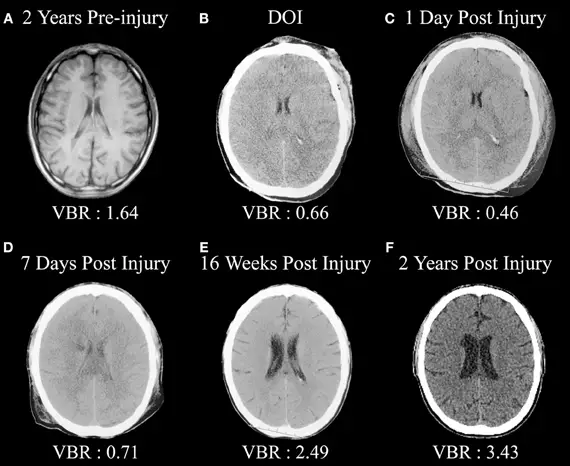

According to the CDC Traumatic Brain Injury report contribute to about 30% of all injury-related deaths. Traumatic brain injuries are disproportionately found through brain injury MRI in the very young and the elderly, mainly as a result of falls. Other risk factors/causes of brain-related injuries include motor vehicle brain injury crashes, which account for most of the injuries to those ages 15-44, and physical assaults, which accounted for approximately ten percent of all traumatic brain injuries. Additionally, men are three times more likely than women to receive a traumatic brain injury.